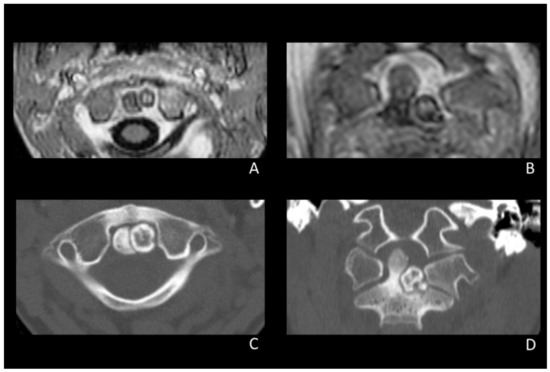

2.1.1. Clinical Presentation, Diagnosis, and Initial Conservative Therapy

2.1.2. Surgical Procedure

2.1.3. Post-Operative Course and Follow-Up